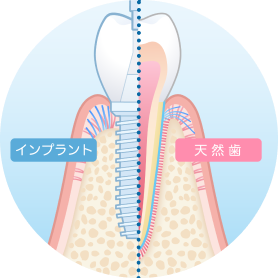

歯周病とインプラントの怖い関係・・・